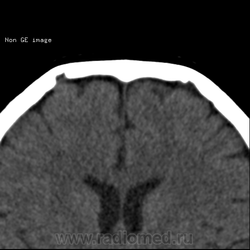

Изменение костей черепа, КТ.

Нейрохирург принес на консультацию снимки. Пациенту был выставлен диагноз в частном диагностическом центре эозинофильная(-ные) гранулёмы лобных костей. Как вам?

А, не совпадают ли эти "гранулёмы" топографически с венозными выпускниками?

Пахионовы ямки. Валентин Львович, Вы первый.

Согласна, конечно пахионовые грануляции.

Конечно же это не эозинофильные гранулёмы, пациента прислали к нейрохирургу, предварительно расстроив.

Вижу эти образования как ямочки грануляций, сообщающиеся с диплоетическими венами

Пахионовы грануляции, конечно! Еще они иногда вдаются в просвет венозных синусов, и тогда рентгенологи пишут "тромбоз")